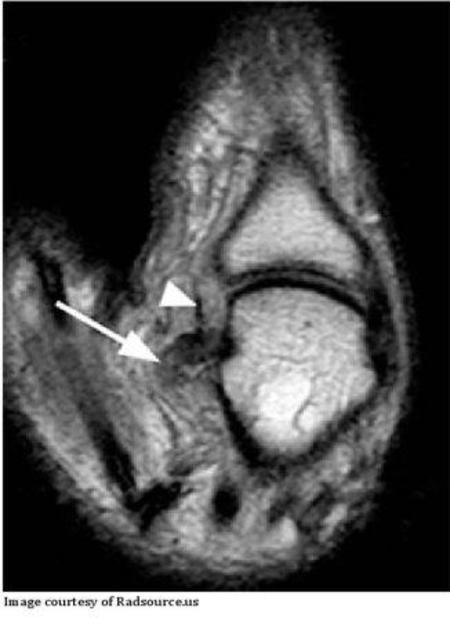

sign?

dx?